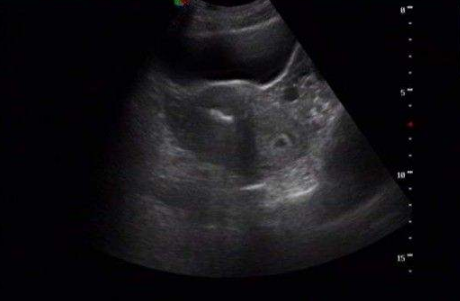

雙角子宮圖片

A:雙角子宮是一種子宮發育畸形的狀態,主要是患者子宮底部融合不完全導致的,患者進行B超或者是宮腔鏡檢查能夠發現子宮和正常女性相比不規則。嚴重的雙角子宮患者也有可能會伴有明顯的腹痛,或者來月經期間有痛經症狀。患者在懷孕時容易造成胎位不正,胎兒不能……

A:雙角子宮根據宮角在宮底水平融合不全的程度,分為完全性的雙角子宮和不全性雙角子宮。一般情況下,雙角子宮是沒有臨床症狀,所以不易發現。有時候雙角子宮會合併有月經量多或者是不同程度的痛經。行婦科檢查的時候可以觸及宮底部是有凹陷的,一般都是通過超聲……

A:雙角子宮是子宮發育異常的其中一種,也是臨床上比較常見的。雙角子宮在臨床上根據宮角在宮底水平融合不全的程度,可分為完全雙角子宮和不完全雙角子宮。在臨床上一般並無特殊症狀,雙角子宮可有月經較多,或者伴有不同程度的痛經症狀。一般通過超聲檢查或者磁……